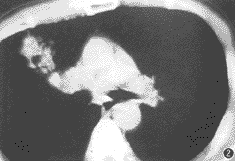

第35例——右肺门斑片状致密影